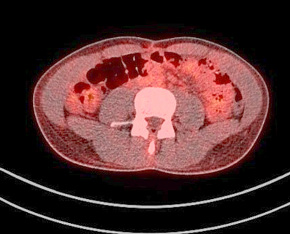

A contrast enhanced CT scan was indicated due to the palpable abdominal tumor and it revealed a formation that originates from the ileal mesentery involving the ileocolic artery and a part of the ileum with ileal wall thickening and partial obstruction (Figures 2, 3 and 4).

24.jpg Figure 2 23.jpg Figure 3

25.jpg Figure 4